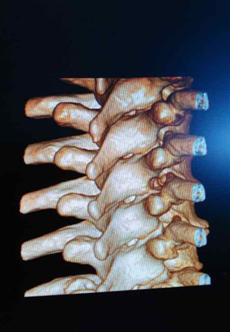

(三维图像)